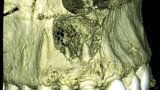

Fig. 2a: Conventional radiograph of an endodontically treated tooth #11 and cold-sensitive tooth #12 compared with CBCT imaging showing the presence of a large apical bone defect (taken at a two-day interval).

Fig. 2b: Conventional radiograph of an endodontically treated tooth #11 and cold-sensitive tooth #12 compared with CBCT imaging showing the presence of a large apical bone defect (taken at a two-day interval).

Fig. 2c: Conventional radiograph of an endodontically treated tooth #11 and cold-sensitive tooth #12 compared with CBCT imaging showing the presence of a large apical bone defect (taken at a two-day interval).